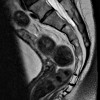

Магнитный резонанс копчика Неинвазивный метод сканирования слоя за слоем нижней части позвоночника с использованием электромагнитного поля с последующей фиксацией данных, полученных с помощью специального оборудования. Он используется для визуализации костей копчика и окружающих мягких тканей, нервов, кровеносных сосудов. Используется для диагностики воспалительных и деструктивных изменений в костях и тканях, окружающих кости копчика. Предназначен для выявления посттравматических переломов и патологий, структурных аномалий, различных типов объемных образований Методика использовалась при подготовке пациентов к операциям на тазовой области. Возможно, МРТ-сканирование копчика с контрастностью и без нее, специальной подготовки к исследованию не требуется.

МРТ сoccyx основана на свойстве атомов водорода в клетках организма изменять свою полярность под воздействием электромагнитных волн в постоянном магнитном поле. Изменения регистрируются датчиками томографа и передаются на специальный компьютер в виде изображений отдельных слоев. Этот метод используется в диагностике со второй половины 20-го века и является одним из приоритетов при углубленном осмотре нижней части позвоночника. МРТ-копчик позволяет получать изображения с высоким разрешением, которые позволяют выявлять опухоли на ранних стадиях, а также выявлять хронические переломы копчика, которые часто отсутствуют в обычной рентгенографии.